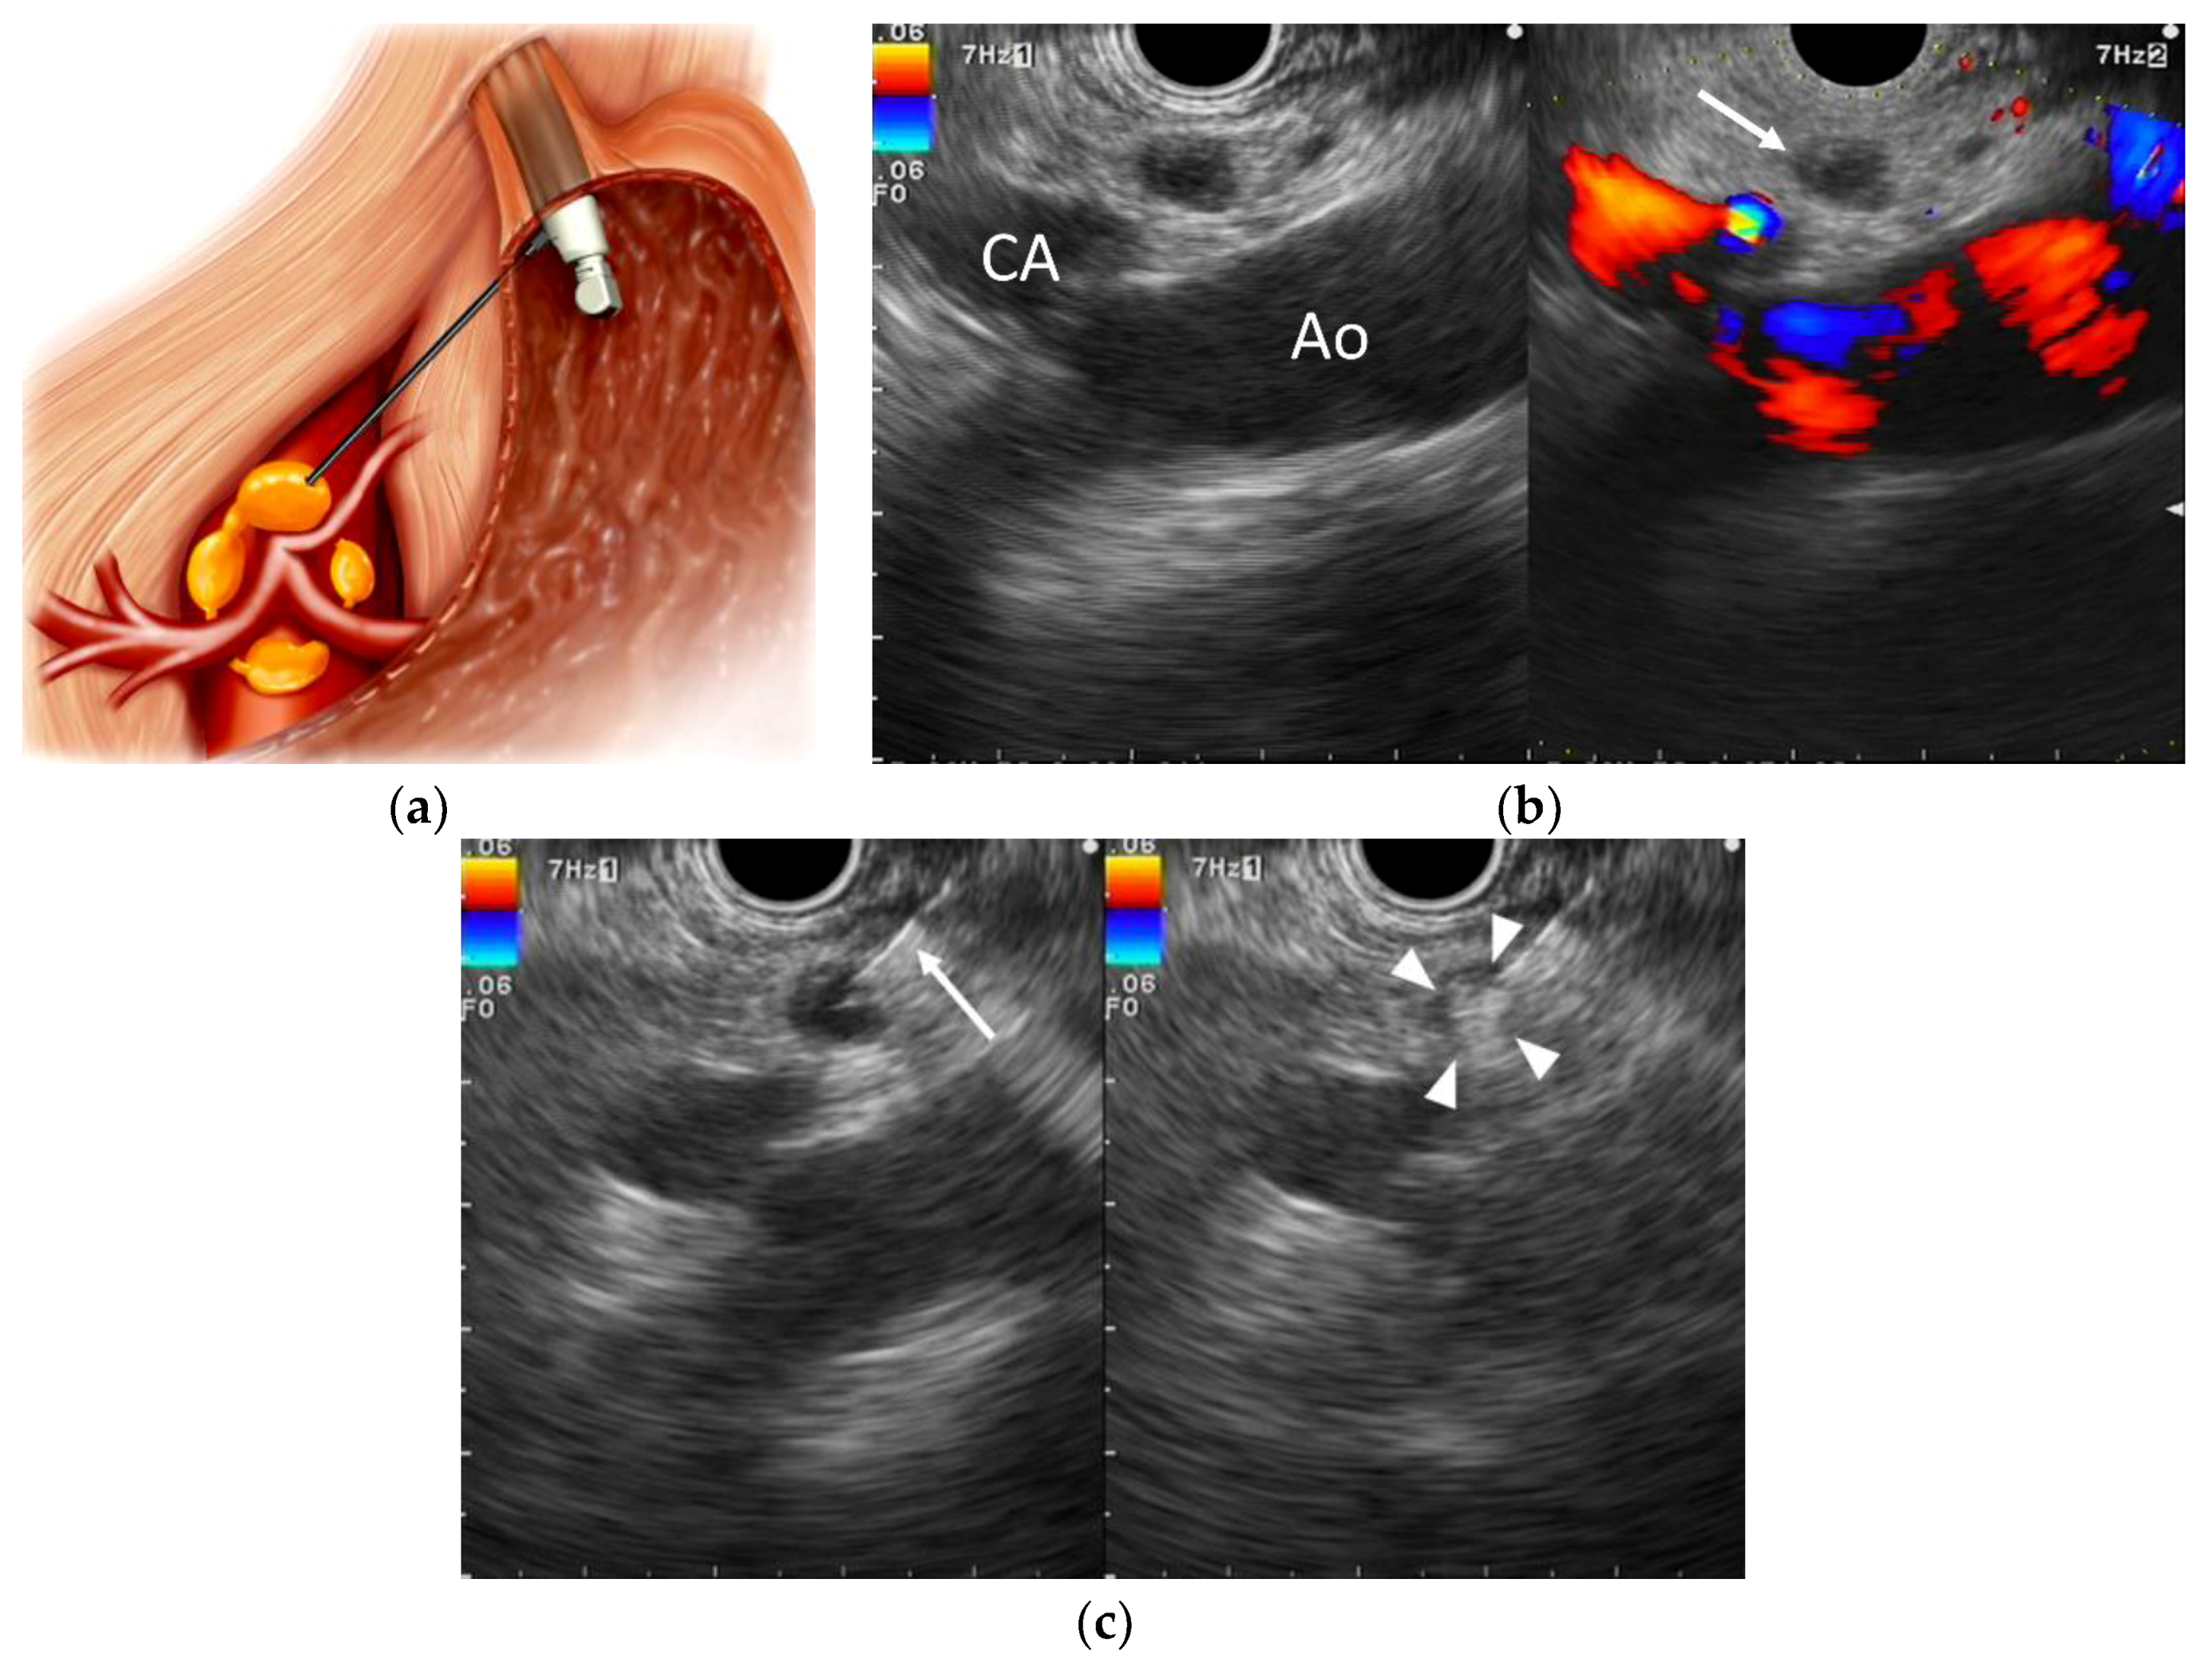

Endoscopic ultrasound image of pancreatic cancer confirmed by (a Endoscopy Biopsy Pancreatic Cancer Doctors can also biopsy a tumor during an endoscopy. Other biopsy types, such as a brush biopsy or forceps biopsy, can be done during an endoscopic cholangiopancreatography (ercp). Biopsy is indicated for patients requiring differential diagnosis with benign chronic pancreatitis or a histological diagnosis, such as patients initiating chemotherapy (cht);. In a brush biopsy, a small brush passes through the.. Endoscopy Biopsy Pancreatic Cancer.

Images of endoscopic ultrasound in advanced pancreatic cancer (a Endoscopy Biopsy Pancreatic Cancer The doctor passes an endoscope (a thin, flexible, tube with a small. In a brush biopsy, a small brush passes through the. Your doctor takes a biopsy. Doctors can also biopsy a tumor during an endoscopy. During this procedure, a doctor. The most sure way of diagnosing pancreatic cancer is by taking a biopsy and looking at it under a. Endoscopy Biopsy Pancreatic Cancer.